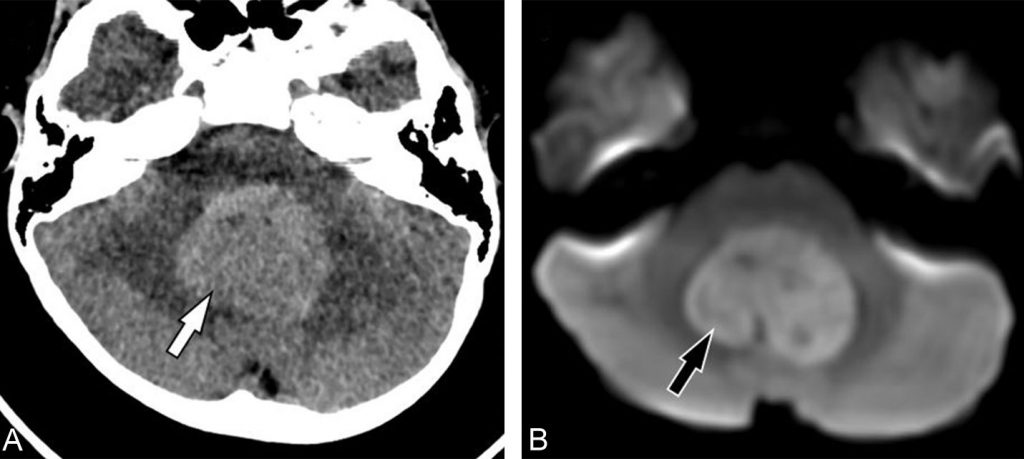

La mise en évidence d’une tumeur médiane de fosse postérieure spontanément hyperdense est caractéristique du médulloblastome (figure 113.1) et doit faire réaliser en urgence une IRM craniospinale avec injection de produit de contraste. L’injection d’un produit de contraste au scanner n’est de fait pas utile au diagnostic.

Fig. 113.1 TDM et IRM cérébrales. TDM cérébrale sans injection (A) montrant une tumeur de fosse postérieure médiane (flèche blanche). Le caractère spontanément hyperdense est en rapport avec l’hypercellularité des médulloblastomes. IRM cérébrale (B) en séquence de diffusion montrant également le caractère hautement cellulaire de ces tumeurs malignes sous forme d’un hypersignal B1000 (flèche noire).

Source : CERF, CNEBMN, 2022.

La lésion est de siège médian dans 80 % des cas (développée au niveau du vermis) et latérale dans 20 % des cas (développée dans un hémisphère du cervelet). La lésion est tissulaire, hautement cellulaire en séquence de diffusion (figure 113.1), et se rehausse après injection de produit de contraste (figure 113.2). L’injection de gadolinium est indispensable pour rechercher des métastases leptoméningées cérébrales (figure 113.2) et médullaires.